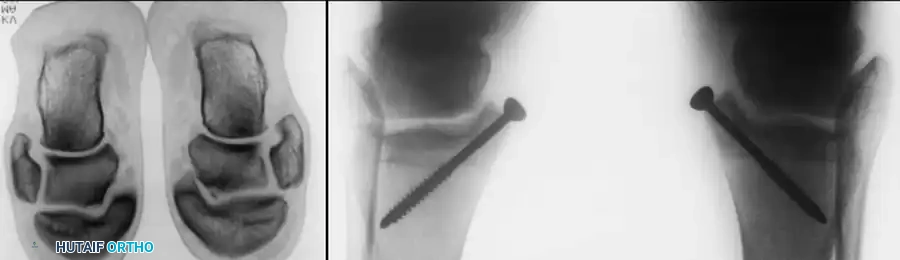

Fig. 16: Preparation for an OATS procedure. A medial malleolar osteotomy is performed to gain perpendicular access to a large posteromedial lesion.

Fig. 17: Step-by-step OATS technique. The recipient site is cored out, and the donor plug from the knee is carefully impacted into the talar defect, ensuring flush alignment with the surrounding native cartilage.

3. Structural Allograft and Advanced Techniques

For massive, uncontained lesions or severe cystic degeneration, structural fresh osteochondral allografts are utilized. These require meticulous size-matching and rigid internal fixation.